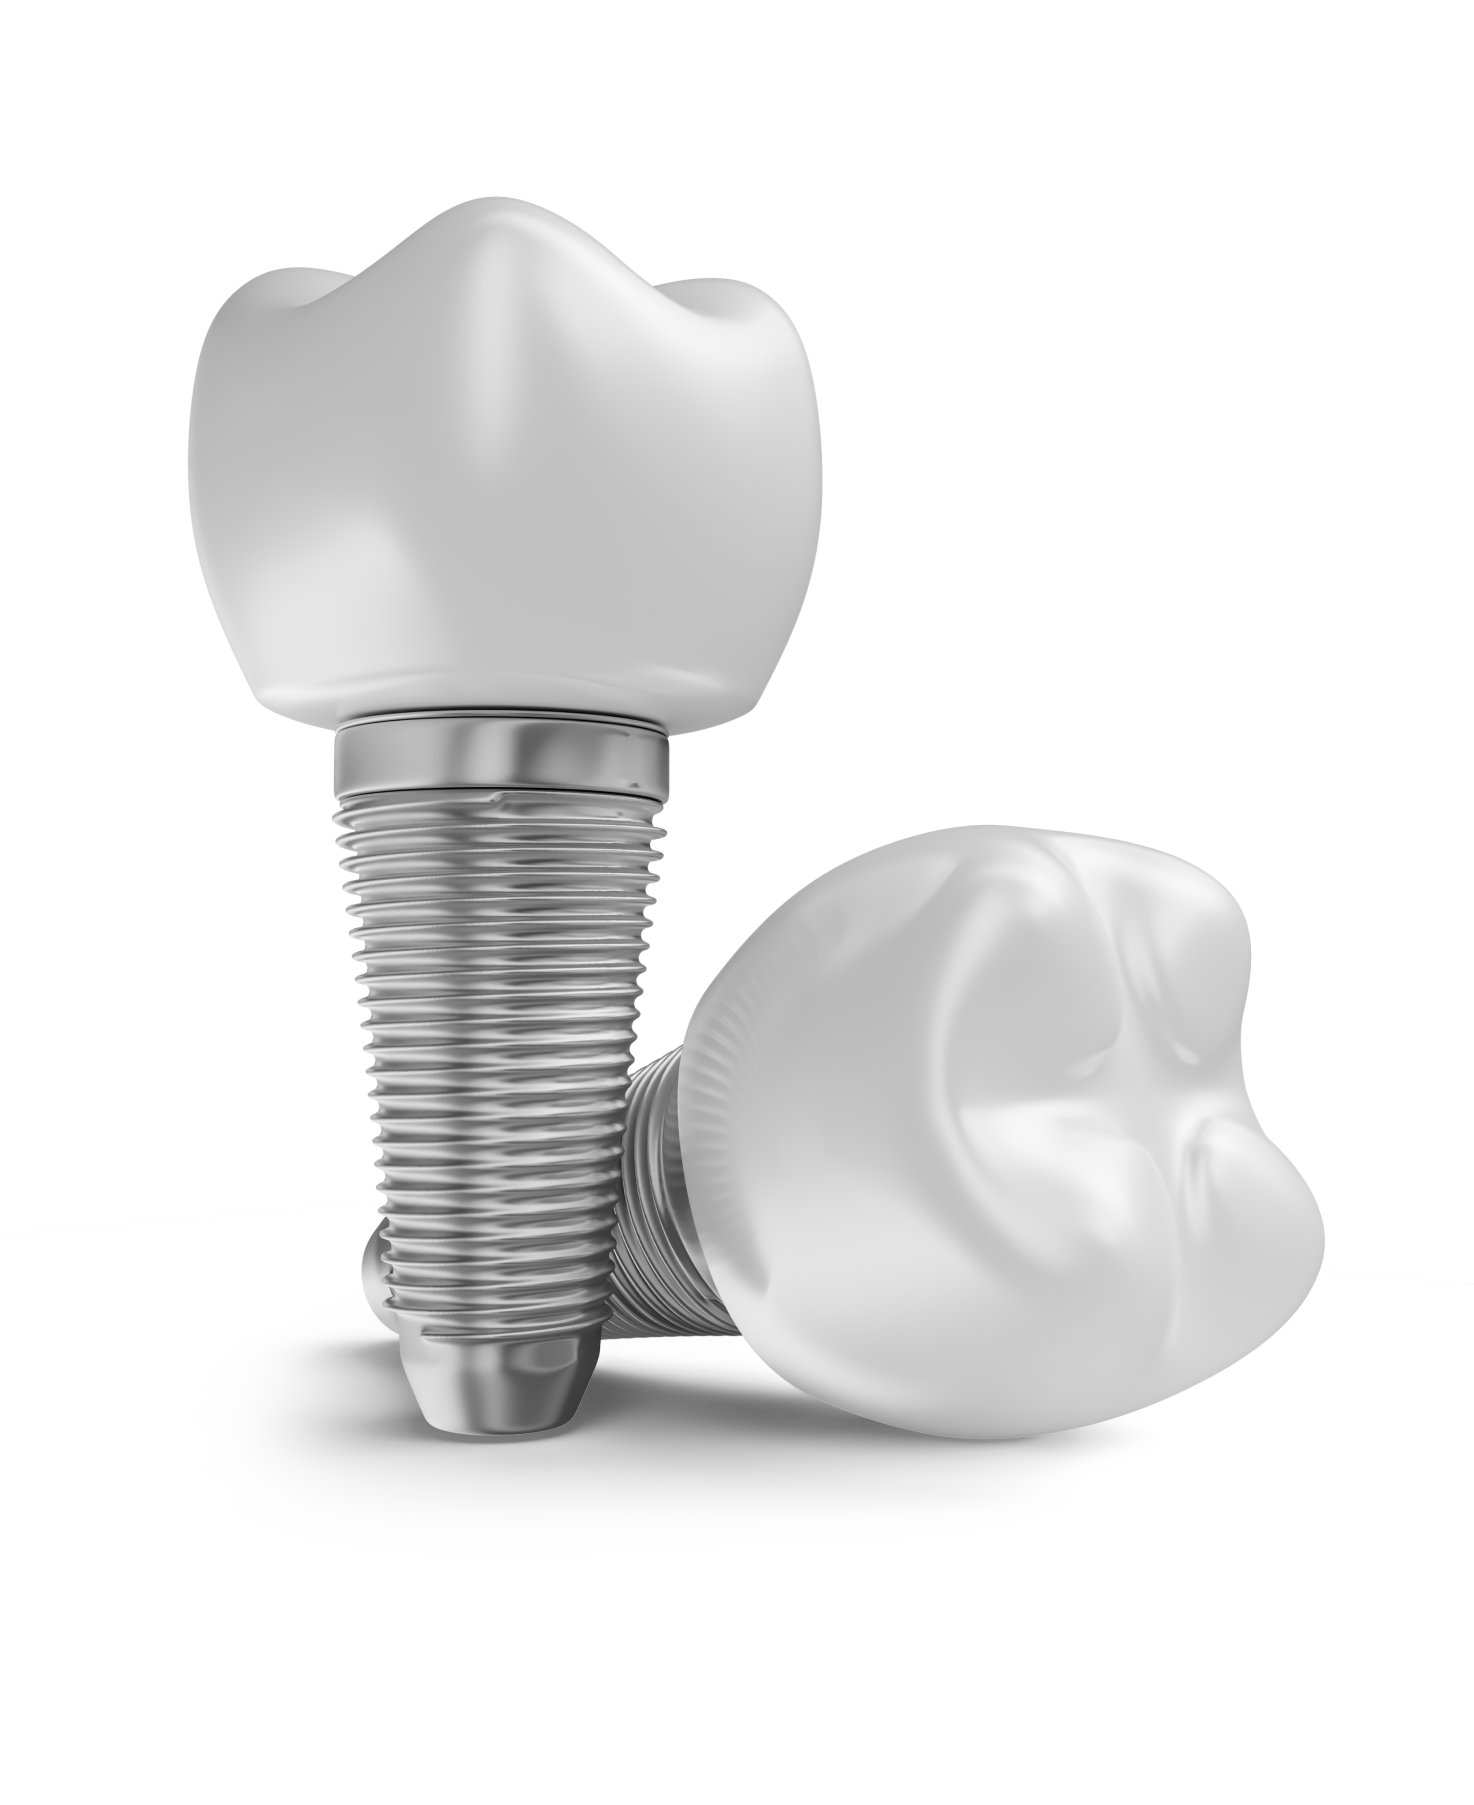

Рентген имплантов Alpha Bio: диагностика и качество